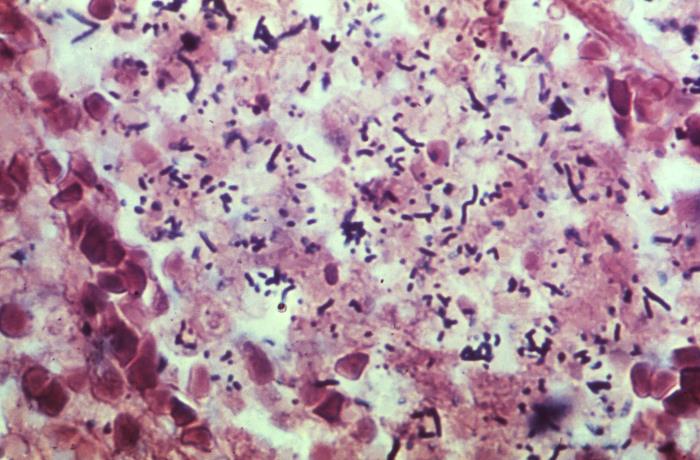

显微镜下的李斯特菌

生物显微镜下李斯特菌呈单个或短链状

多数李斯特菌体***端较大,似棒状

培养时间延长或粗糙型培养可呈丝状菌体